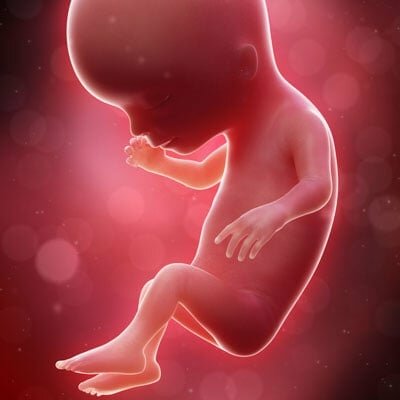

• 1st Trimester

1st Trimester

Months 1 through 3. Implantation occurs about one week after conception when the zygote nestles into the endometrium. This trimester is where the embryo develops most of the necessary vital organs. By the end of month 3, the fetus measures to be about 3 inches in length and weighs roughly 1/2 an ounce. From this point on, no new organs will be formed, the current organs will need to develop more.

• 2nd Trimester

2nd Trimester

Months 4 through 6. The size of the fetus at the start of this trimester is about 5 inches in length and roughly 4 ounces in weight. This trimester is where the features of the fetus start to resemble that of a human being. By month 5 the fetus' limbs, muscles, and nerves are stronger and more developed which is why the mother can feel the turns, stretches, and kicks during what is known as the quickening. By the end of the 2nd trimester the fetus weighs about 1 1/2 - 2 lbs and 9 inches long

• 3rd Trimester

3rd Trimester

Months 7 through 9, the last trimester. At the start of this trimester the fetus is about 10-12 inches in length and weighs around 2-3 pounds. Throughout this trimester the fetus will grow an additional 3-4 inches and gain about 6-8 pounds. The organs increase their activity and the development of limbs, nerves, and muscles will strengthen its ability to move on its own.